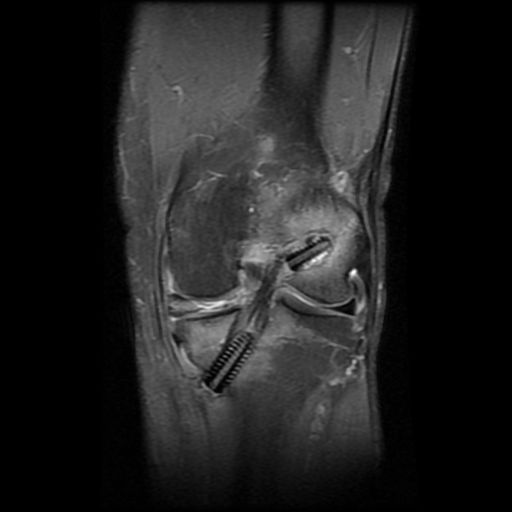

Bu dokular açık cerrahi ile alınır. Bunun için yaklaşık 3-4 cm lik küçük kesiler kullanılır. Daha sonra artroskopik olarak (gelişmiş merkezlerde) diz içindeki ACL artıkları temizlenir ve ACL nin orjinal yerlerine uyan tibia ve femur kemiklerine 2 tünel açılır. Bu tüneller içine alınan doku yerleştirilir ve uygun gerginlikte tünellere vida, tel çivi gibi maddelerle fikse edilir. Ameliyat sonrası genellikle dizlik uygulanır.

erdincmordumanaclintrafix